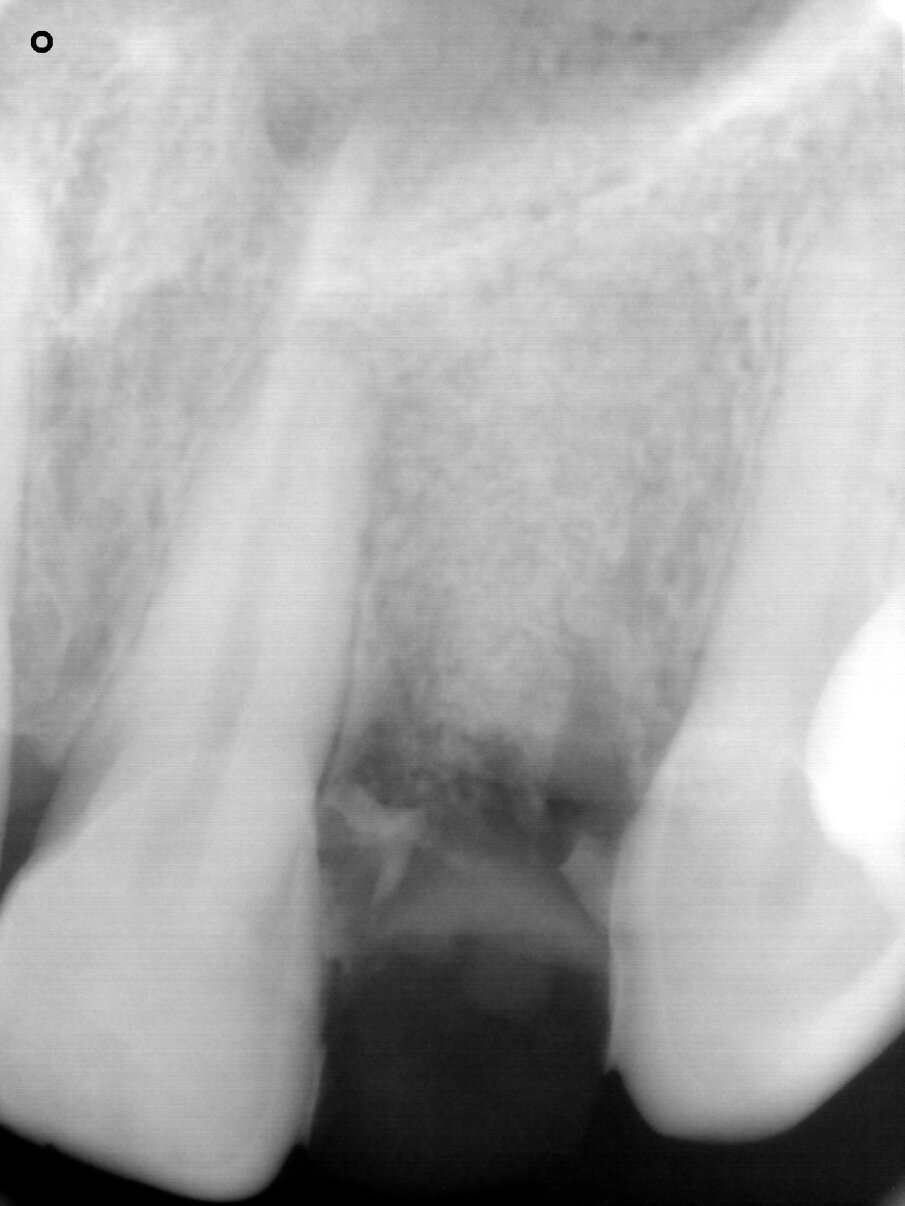

A 48-year-old male patient presented with a horizontal fracture of tooth #22 (Fig. 1). He complained of swelling of the tooth’s periapical area, and the periapical radiograph revealed a horizontal fracture with an unfavourable root–crown ratio (Fig. 2).

Fig. 2: Periapical radiograph showing the horizontal fracture of the endodontically treated tooth #22 and an unfavourable root–crown ratio.